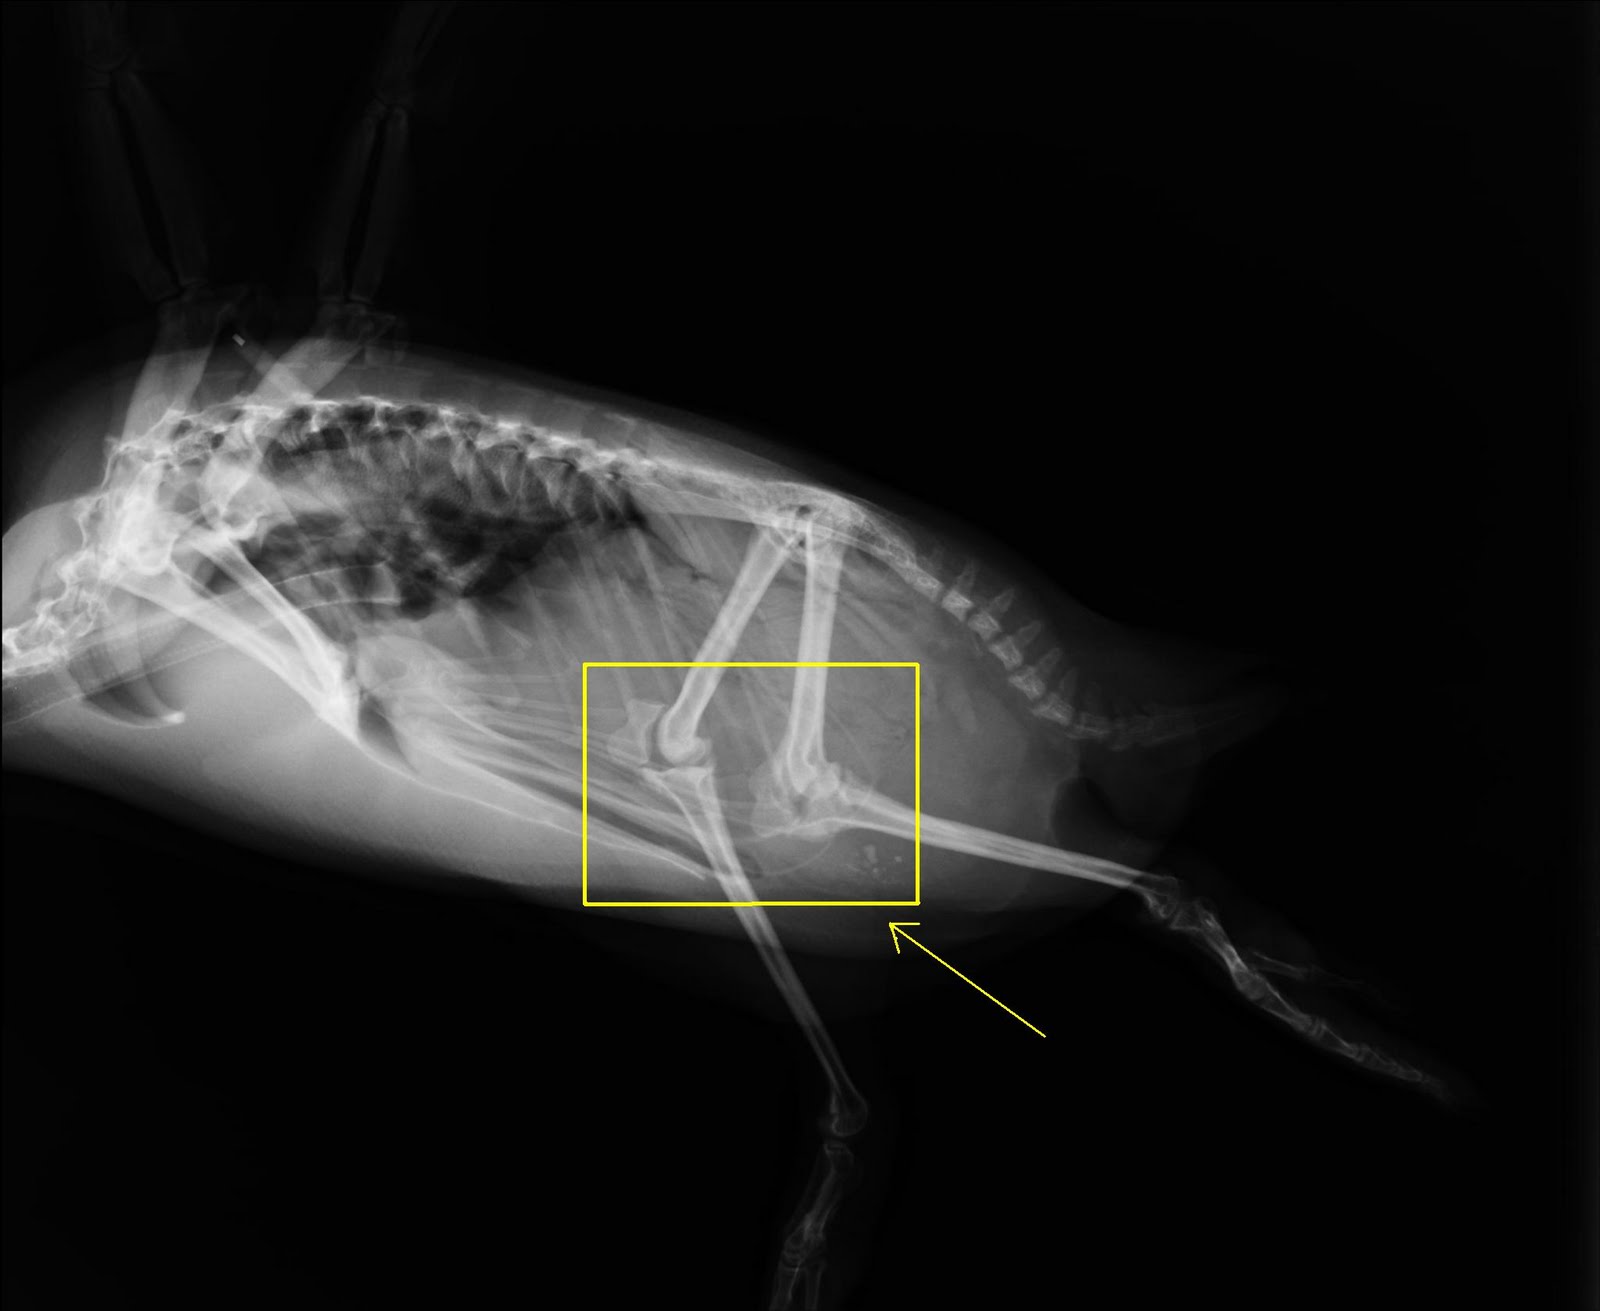

Do penguins have knees?

In short, the answer is yes, they do. Actually, a penguin’s leg is not much different from our own. They have a femur, a tibia, a fibula, and (of course) knees. Penguins also actually have much longer legs than they appear too. The upper leg is covered by feathers because, well, if you lived in the Arctic, I’m pretty sure you’d want your thighs covered as well.